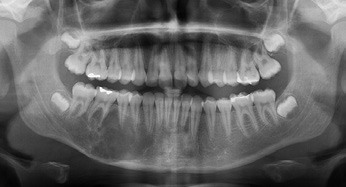

Die zur Verfügung stehenden radiologischen Untersuchungstechniken wie Panoramaschichtaufnahme (OPG)/intraorale Aufnahmen, Computertomographie (CT), Positronenemissionstomographie (PET), PET/CT, dentale Volumentomographie (DVT) und Magnetresonanztomographie (MRT) werden durch nicht radiologische Verfahren wie Ultraschall sowie Knochenszintigraphie ergänzt, können aber die klinische und histologische Untersuchung als wichtigste diagnostische Maßnahmen nicht ersetzen.

- Die Computertomographie (CT) ist nach wie vor das am häufigsten angewendete Verfahren. Die Vorteile liegen in einer guten Darstellung der Tumorläsion, des umgebenden Weichgewebes und der möglichen Knocheninfiltration. Andrle et al. konnten feststellen, dass die Computertomographie eine hohe Spezifität in der Erkennung von Knocheninfiltration aufweist (Quellenangabe). Ebenso weist die CT eine hohe Sensitivität in der Erkennung von besonders kleinen Arealen der Knocheninfiltration auf [7]. Nachteile der CT sind die geringere Auflösung, die hohe Strahlenbelastung sowie die ausgeprägten Metallartefakte, wie z. B. bei metallischen Restaurationen.